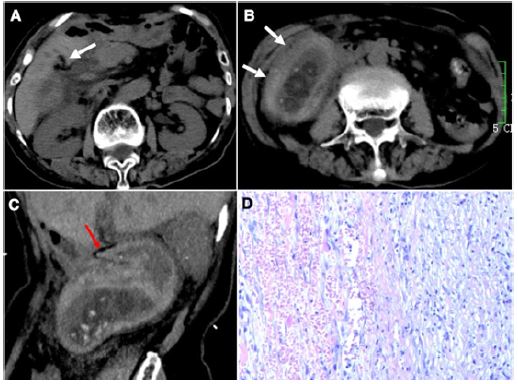

An 85-year-old woman presented with progressive abdominal pain and vomiting for 4 days. Her past medical history was unremarkable. On physical examination, she had tenderness in the right lower quadrant of the abdomen without rebound or guarding. Laboratory test showed a slightly elevated white cell count of 10.5×109/L with 84.3% neutrophils. Urgent non-contrast Computed Tomography (CT) scan of the abdomen revealed a conspicuous “whirl” sign at the the cystic pedicle, a distended and horizontally displaced gallbladder with a thickened, hyperattenuating wall, and an abrupt angulation of gallbladder neck (Figure 1A-1C). At emergency laparotomy, the gallbladder was gangrenous and rotated around its pedicle in a 540° clockwise manner. De-torsion and cholecystectomy were performed. Histologic examination showed extensive transmural hemorrhagic necrosis (Figure 1D). The patient recovered well postoperatively.

Figure 1: (A) Axial unenhanced CT image revealing a classic “whirl” sign at the gallbladder fossa (arrow), pathognomonic for a gallbladder torsion. (B) Axial unenhanced CT image showing a distended and horizontally displaced gallbladder with diffusely thickened, spontaneously hyperattenuating wall (arrows), suggestive of a free-floating, necrotic gallbladder. (C) Oblique sagittal reconstruction CT image showing lower position of gallbladder in the right lower quadrant, with an abrupt angulation of its neck (arrow). (D) Pathological histology showing haemorrhagic necrosis of gallbladder wall, consistent with a gangrenous gallbladder.

Gallbladder torsion, usually occurring in elderly women, is a rare abdominal emergency with a reported mortality up to 6% [1]. Early diagnosis is the key to preventing potentially fatal sequelae, such as gallbladder perforation. The clinical presentation is often non-specific, which makes this condition easily confused with acute abdomen. Just like our case, gallbladder torsion mimics the clinical picture of appendicitis owing to the lower position of gallbladder. Although it is rare, clinicians must remain alert to the possibility of gallbladder torsion in those patients with right lower quadrant pain [2]. CT is recommended if this pathology is suspected. This patient portrays classic CT signs: (1) a “whirl sign” pathognomonic for gallbladder torsion; (2) diffusely thickened wall with haemorrhage, indicating gangrenous cholecystitis secondary to vascular compromise [3,4].